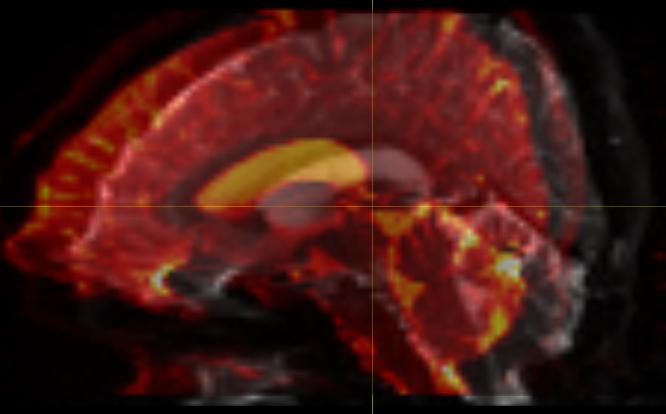

I then processed both data and created the whole brain TDI images, but

the results are quite different (see tdi_analyze.jpg and

tdi_nifti.jpg).  It appear the TDI image by using ANALYZE is what TDI

is supposed to be looked like although now it does not align with

original NIFTI data, which has made the previous co-registration

matrices useless.